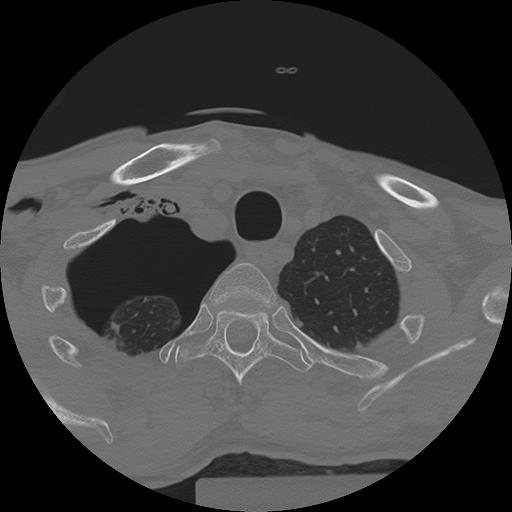

11 HUESO,,Axial,2.0,HUESO,,